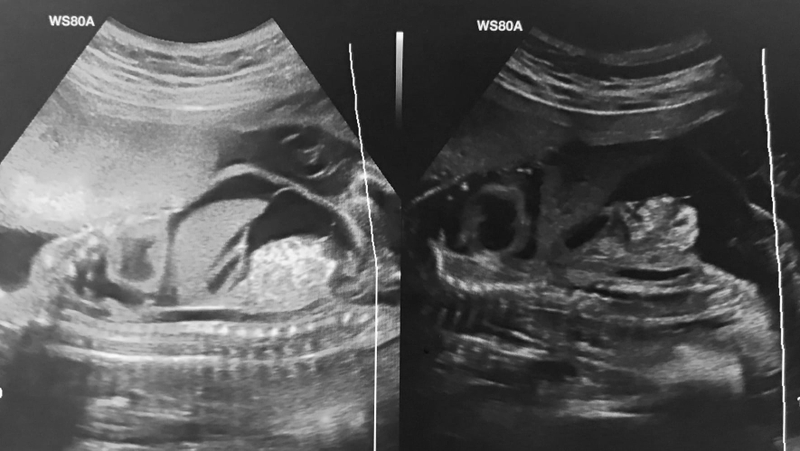

Việc chẩn đoán hội chứng hygroma kystique thường có thể được thực hiện sớm, khoảng 11 - 12 tuần phát triển của thai nhi, thông qua sàng lọc trước sinh. Phương pháp chẩn đoán quan trọng liên quan đến việc đo siêu âm độ mờ da gáy, cho phép phát hiện những bất thường, chẳng hạn như hygroma kystique qua độ dày sau gáy của thai nhi.

Dấu hiệu chẩn đoán quan trọng nhất đối với hygroma kystique là phát hiện bất thường qua siêu âm:

Biểu hiện này được quan sát qua hình ảnh siêu âm thấy có một khoảng trống tăng lên ở phía sau cổ với sự có mặt của một khối nang thường có đường kính vượt quá 3mm. Phương pháp siêu âm này rất quan trọng để phát hiện sớm biểu hiện bệnh, thường được xác định trong quá trình sàng lọc trước sinh định kỳ.